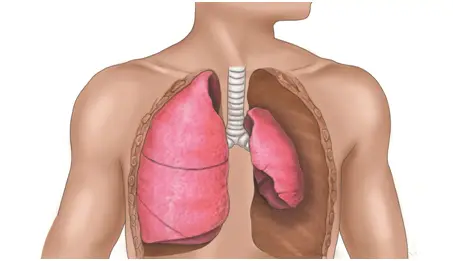

폐는 풍선처럼 숨을 들이마시면 부풀고, 내쉬면 줄어듭니다. 그런데 풍선이 들어 있어야 할 자리에 바람이 새어 나와서 주변 공간(폐와 가슴벽 사이 공간)에 차게 되면, 풍선이 제대로 부풀지 못합니다. 이게 바로 폐기흉입니다. 쉽게 말해, “폐에 바람이 새서 숨을 잘 못 쉬게 되는 상태”라고 할 수 있습니다.

폐기흉의 증상은 폐가 얼마나 갑자기, 또 얼마나 크게 눌리는지에 따라 차이가 납니다. 어떤 사람은 단순히 가슴이 뻐근하거나 숨이 조금 불편한 정도로 끝나지만, 다른 사람은 생명을 위협하는 심각한 호흡곤란까지 겪을 수 있습니다.

겉으로 드러나는 변화로는 숨을 쉴 때 한쪽 가슴이 잘 움직이지 않거나 덜 부풀어 오르는 것이 관찰될 수 있습니다. 심한 경우에는 입술이나 손끝이 파랗게 변하는 청색증이 나타날 수 있는데, 이는 몸에 산소가 부족하다는 신호입니다.